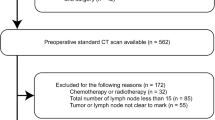

Patients (228) with newly diagnosed rectal cancer, confirmed by biopsy, underwent enhanced computed tomography (CT). Patients were assigned to the benign node or malignant node group according to histopathological analysis of node samples. All CT-detected lymph nodes were segmented using the edge detection method, and seven quantitative parameters of each node were measured. To increase the prediction accuracy, a hierarchical model combining the merits of the support and relevance vector machines was proposed to achieve higher performance.

Of the 220 lymph nodes evaluated, 125 were positive and 95 were negative for metastases. Fractal dimension obtained by the Minkowski box-counting approach was higher in malignant nodes than in benign nodes, and there was a significant difference in heterogeneity between metastatic and non-metastatic lymph nodes. The overall performance of the proposed model is shown to have accuracy as high as 88% using morphological characterisation of lymph nodes.